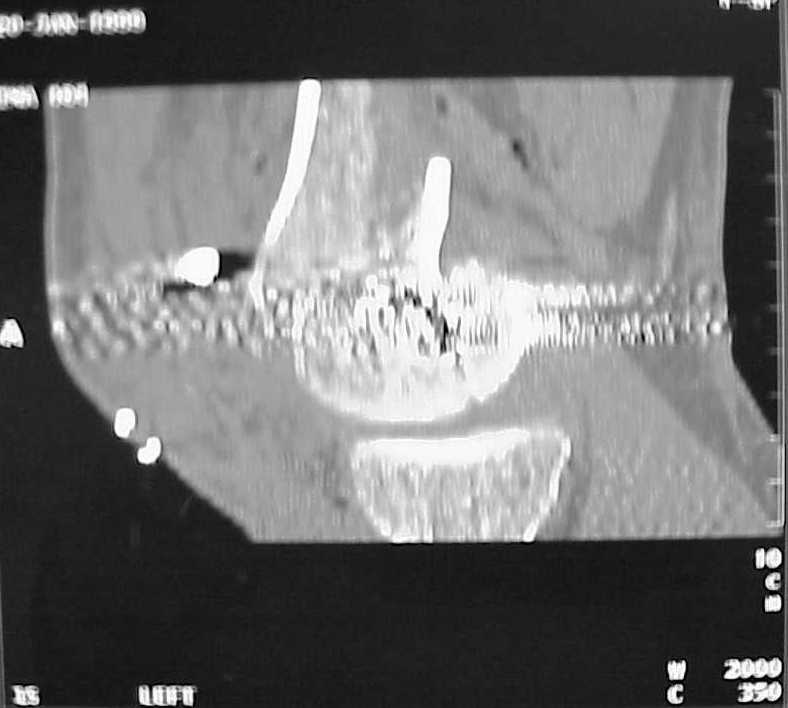

So I think a TAC of the knee could be useful.

A CT and knee xrays would help identify lateral condyle comminution and/or a "hoffa fragment" of the posterior condyle. I am concerned that the lateral cortex is not sufficient to give purchase for a retrograde IMN. blocking screws could improve this as a possibility. A long blade or LISS if avaible would be my secondary choices. Good luck. Any chance you can get these cases transferred earlier when it